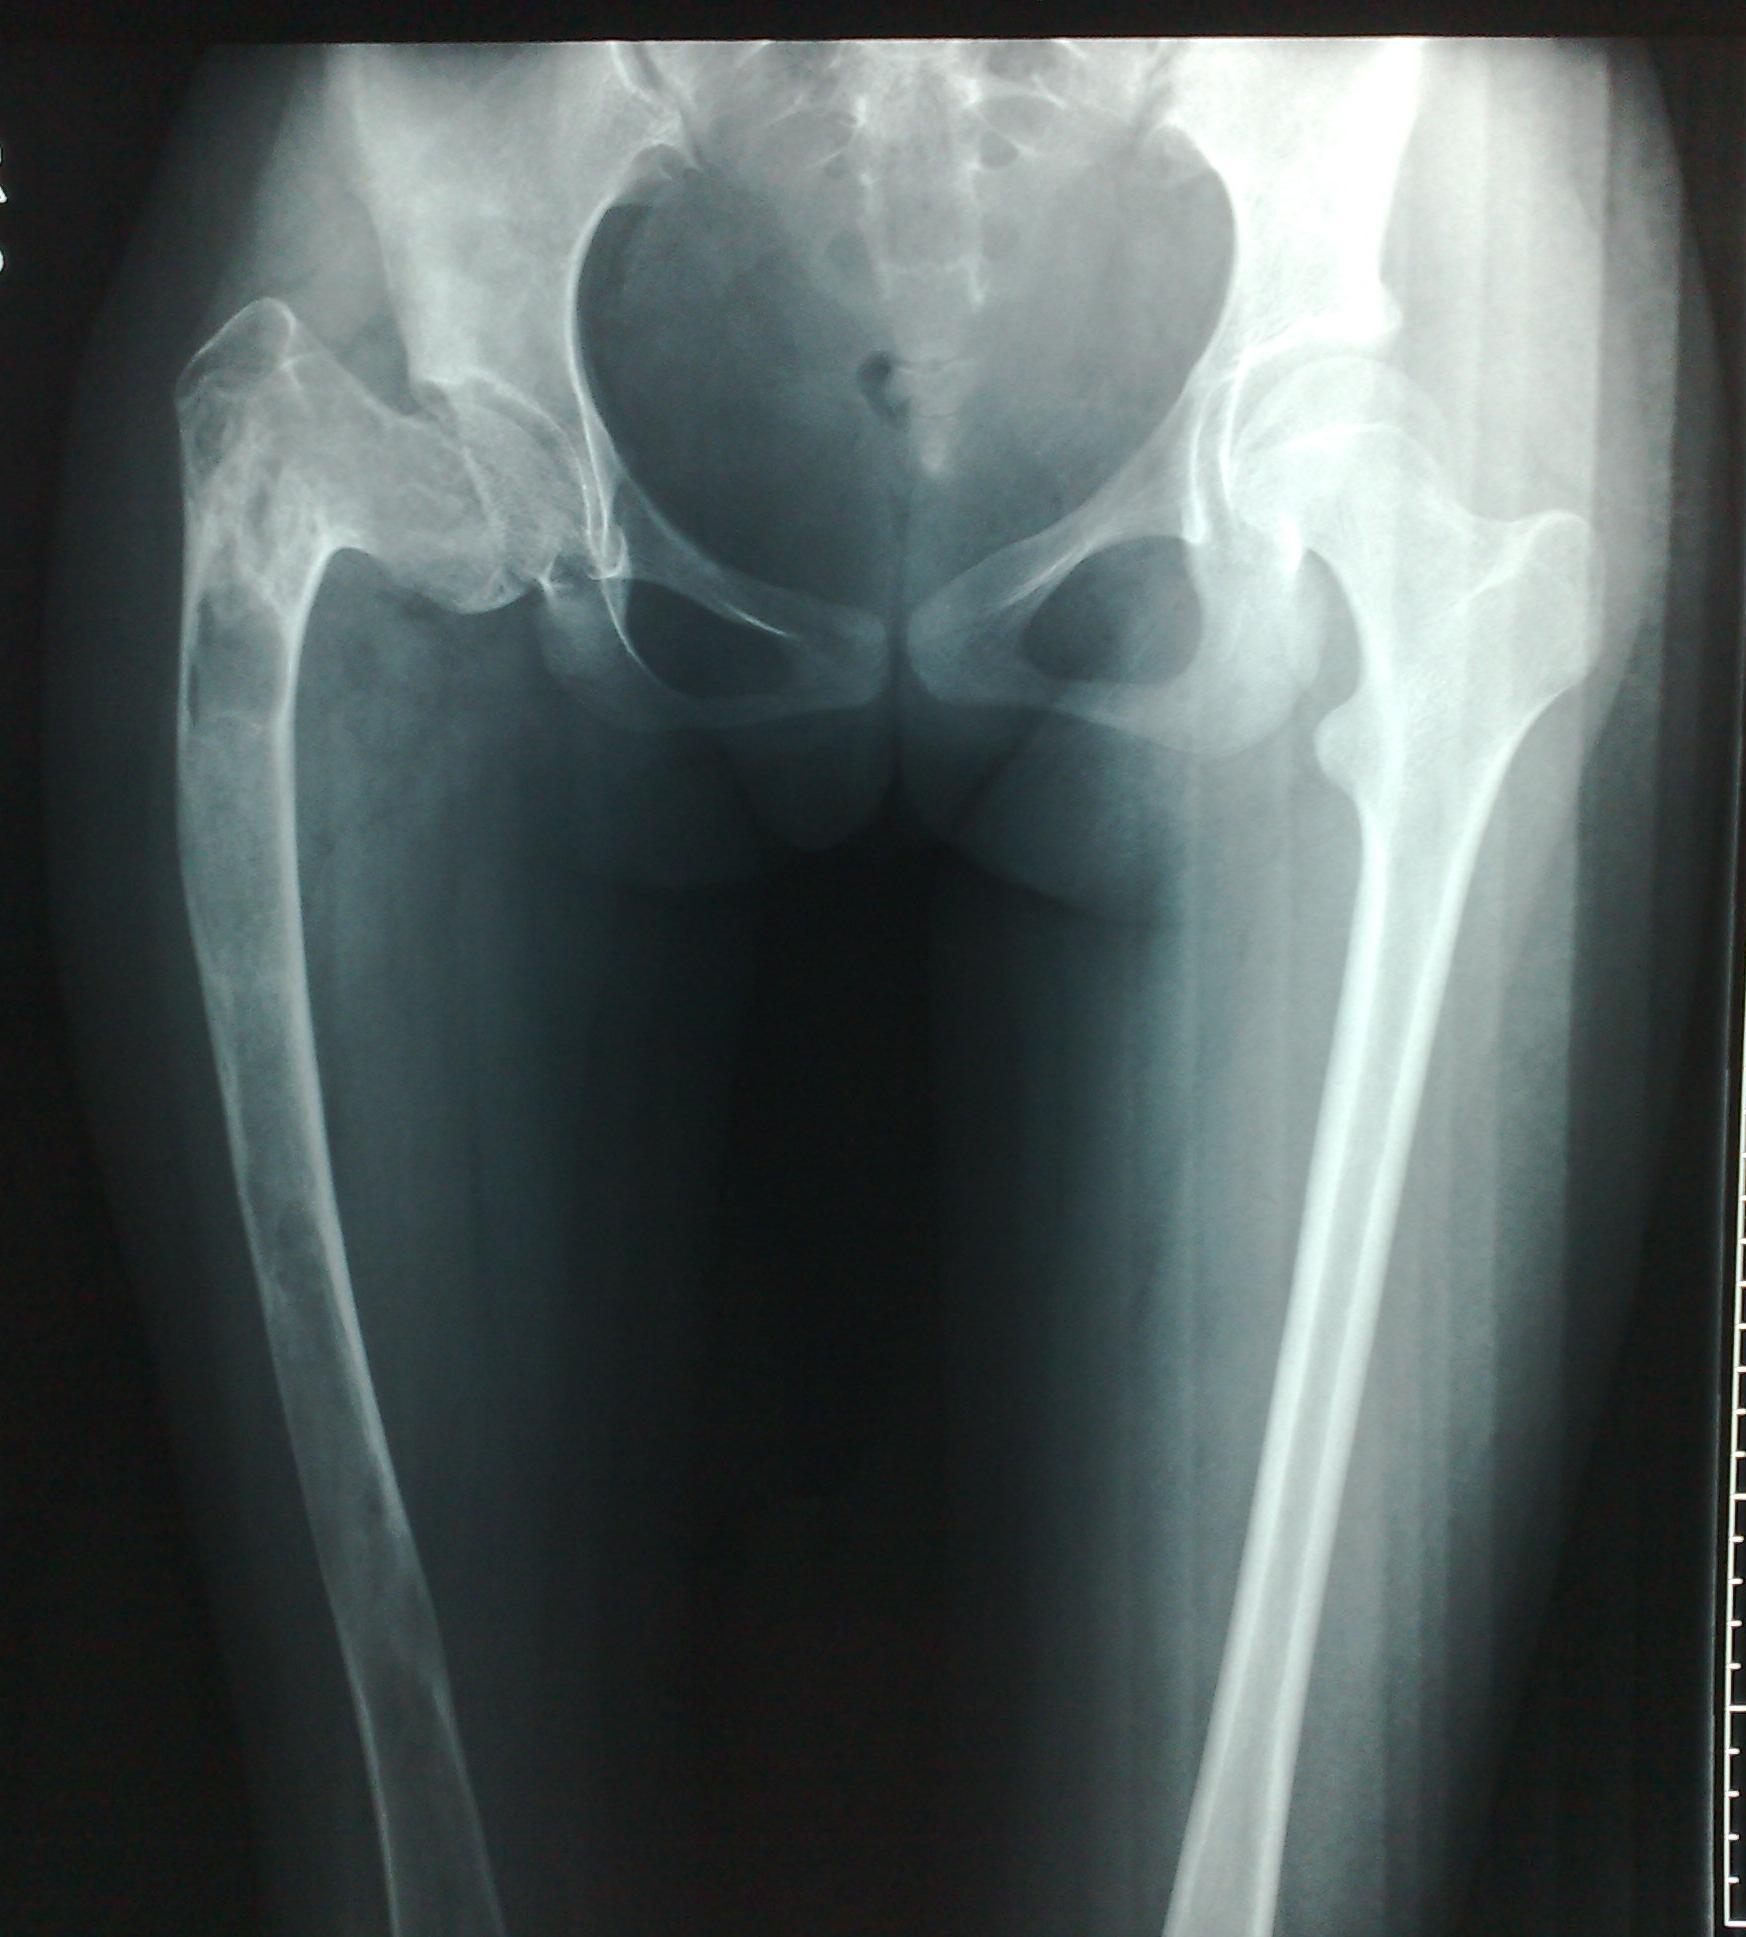

对于严重髋内翻畸形颈干角<60°,且股骨头下方有骨赘形成(如图1),肢体短缩严重者:如果继续使用DHS钢板,力求使颈干角恢复到120°时,此时髋关节头臼咬合已不匹配,臀中肌张力会更大,甚至肢体延长过多会引起坐骨神经症状。对这类患者我们采用DCS钢板,缩减颈干角为95-105°,术后患者髋关节头臼咬合基本匹配,臀中肌经轻度松解也可适应,同时也减少了坐骨神经损伤的风险。26例中我们使用DCS钢板6例,术后均达到满意的效果。

图1女性,18岁,术前肢体短缩9cm图2 术后力线纠正